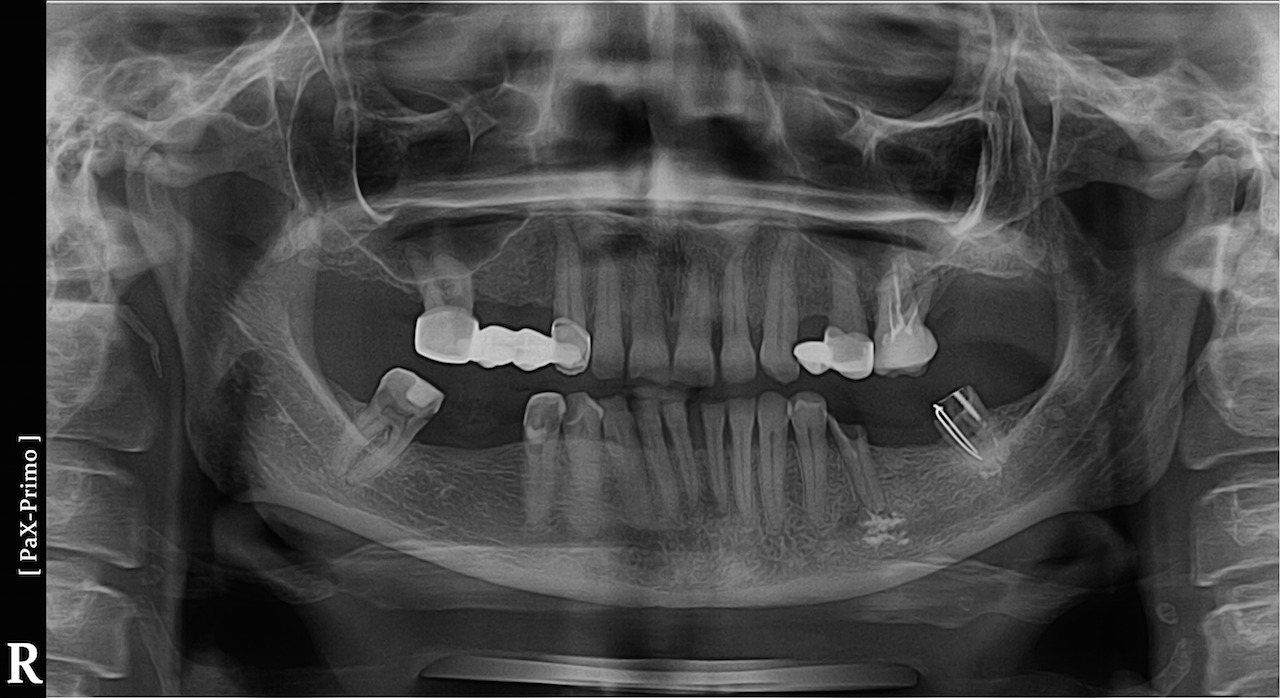

Онемела губа и зубы 87 фото